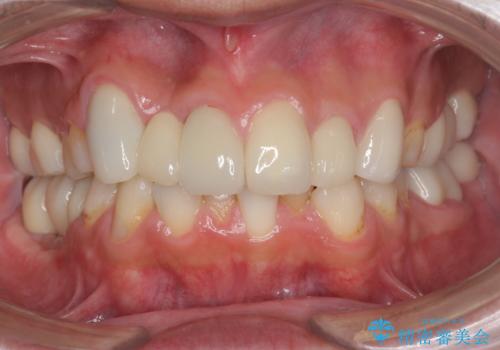

銀歯を白く セラミックインレーに

- 銀歯にしたのが20年以上前とのことで、白くやりかえたいということでした。

セラミックインレーにしています。

- 7万円(左下6 emaxプレスインレー 7万円)費用は治療当時の料金となります